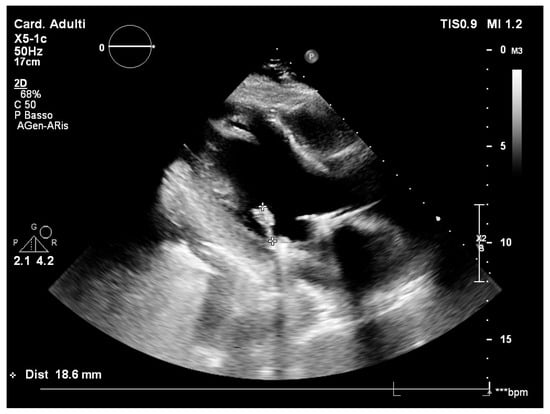

However, a few weeks later, the patient developed recurrent high fever, chills, and general discomfort, prompting another admission to the local emergency room. Routine blood tests showed a significant increase in inflammatory markers. A transoesophageal echocardiography (TEE) was performed, revealing the presence of multiple vegetations on the anterior mitral leaflet, projecting into the left atrium (Figure 1). An empirical but reasoned antimicrobial therapy was started with daptomycin (700 mg intravenously per day) and ceftriaxone (1 g intravenously per day) after collecting the blood culture samples, according to the decision of an infectious disease specialist.

Figure 1.

Transoesophageal echocardiography with mitral valve vegetations. *** transoesophageal.